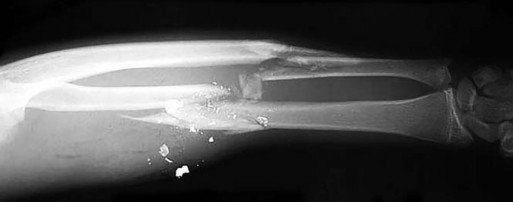

Question 23

A 16-year-old boy presents with progressive knee pain. Radiographs demonstrate a destructive distal femoral lesion with a 'sunburst' periosteal reaction as shown below. Biopsy confirms high-grade intramedullary osteosarcoma. Following neoadjuvant therapy and surgical resection, what is the single most important prognostic factor for long-term survival?

Explanation

The image and presentation are classic for a conventional high-grade osteosarcoma. While factors like tumor size and alkaline phosphatase have prognostic value, the most critical prognostic indicator for overall survival is the degree of histologic necrosis (typically aiming for >90% necrosis) following neoadjuvant chemotherapy.